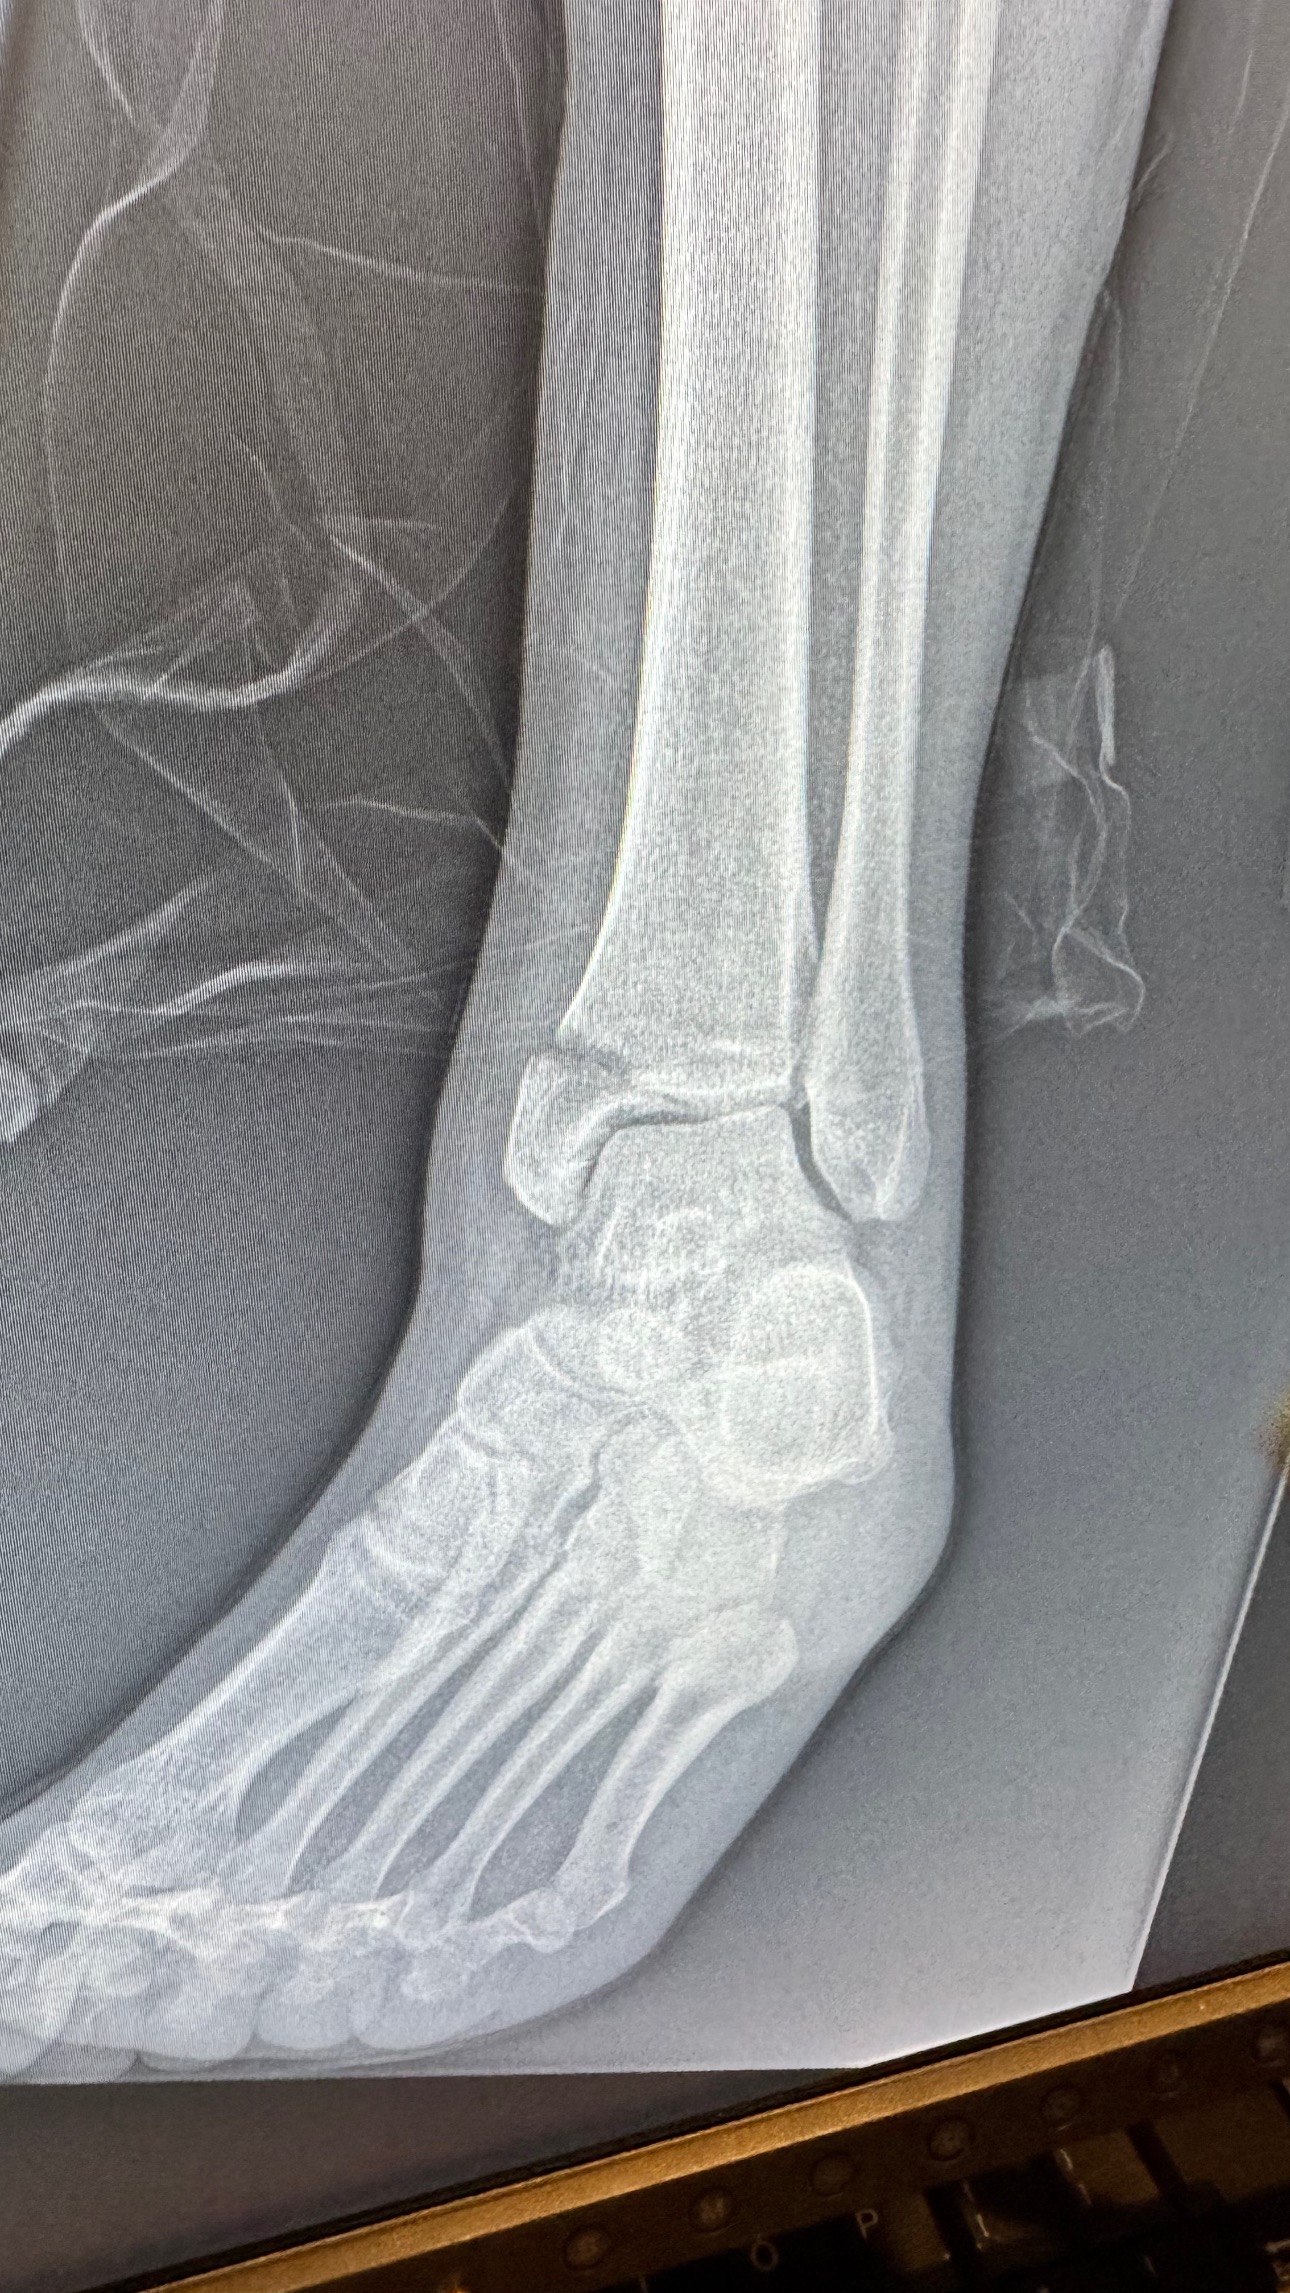

En mayo de 2025, mientras trabajaba, un elevador de tijera de 3,200 libras se descontroló y pasó por encima de mi tobillo, aplastando y destrozando la parte baja de mi pierna. Ese día no solo se rompieron mis huesos, también se quebró mi independencia, mis sueños y la vida que conocía.

Sufrí fracturas múltiples, hemorragias internas y un daño nervioso tan severo que los médicos me diagnosticaron CRPS (Síndrome de Dolor Regional Complejo) — conocido como “la enfermedad más dolorosa del mundo”.

In May 2025, while working, a 3,200-pound scissor lift went out of control and rolled over my ankle, crushing and destroying the lower part of my leg. That day, not only were my bones broken, but also my independence, my dreams, and the life I once knew.

I suffered multiple fractures, internal bleeding, and severe nerve damage that led doctors to diagnose me with CRPS (Complex Regional Pain Syndrome) — known as “the most painful disease in the world.”